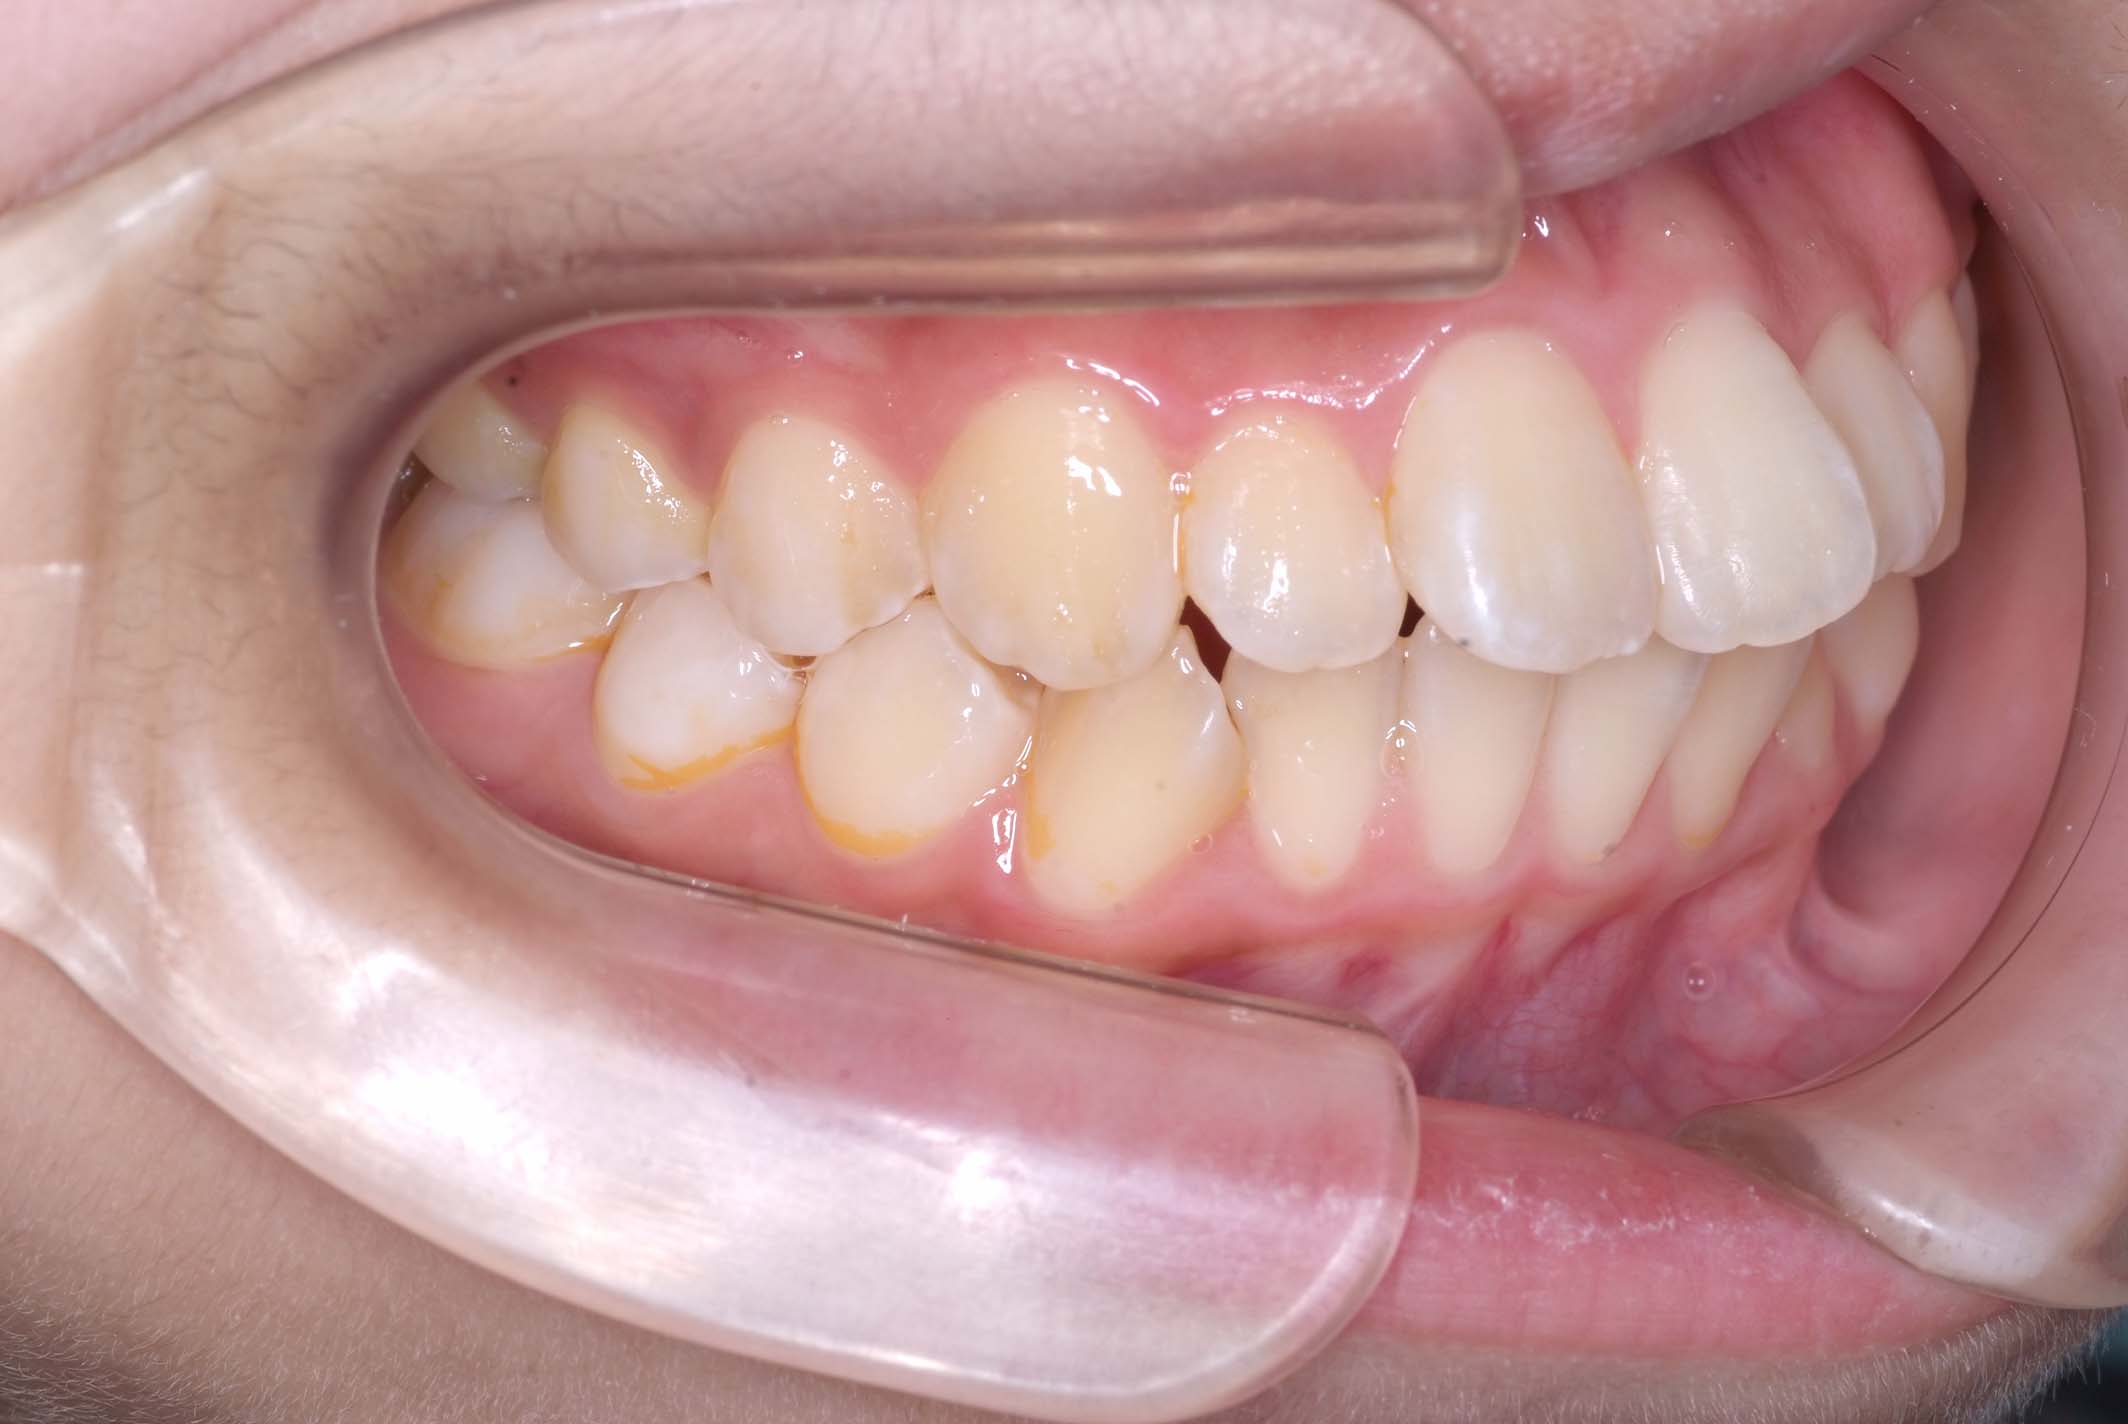

初診時年齢8才の女子で、前歯部開咬を気にして来院されました。

検査の結果、前歯部開咬と正中離開と上下顎前歯唇側傾斜を伴うアングルⅡ級1類不正咬合と診断しました。

前期治療は、リンガルアーチで正中離開を改善し、その後は歯列矯正用咬合誘導装置(マイオブレース)を使用して舌のトレーニングを行いました。後期治療は、上下左右4番を抜歯の上、セルフライゲーションブラケット装置(クリアティ・ウルトラ)で行いました。治療期間は前後期合わせて6年6ヶ月でした。通院回数:60回。